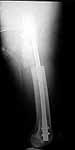

30 y/o man in head-on MVA 12/22/03 sustaining grade II open left femoral midshaft fracture (treated with appropriate staged debridement and retrograde statically locked IM nail), left lateral split tibial plateau fracture (treated with reduction and percutaneous cannulated screw fixation) and comminuted left femoral neck fracture (treated with open reduction and non-compression screw fixation). All initial treatment at another institution and patient recently came to me for follow-up care (he was travelling out of town when he was injured). He has a large (7cm) defect of lateral half of femoral shaft fracture which I plan to pack with a ton of bone graft next week (open fracture site soft tissues healed nicely without sign of infection).

Only small part of femoral shaft fracture visible on one xray. I would be interested in seeing xrays of the shaft fracture. I would be hesitant about bone grafting the femoral shaft fracture early. It might heal. Femoral neck fracture is going to be a problem. I agree, in varus and almost appears with some distraction at the fracture site. I do not think anything now will significantly increase the chance of salvage. I would suggest observation over a reasonable period of time while on crutches, documentation of healing or lack of healing with CT or tomogram (hard to get as the machines are fewer and fewer), then definitive treatment of what is left at the hip. Not an agressive approach but one that gives a 30 year old a chance to heal given how he was initially treated.

I agree that most femoral shaft fractures (even with defects) don't need grafting, but without inclusive films it's difficult to make an opinion regarding this shaft defect.

The issue of the shaft is harder to tell from the images, but could be addressed concurrently or seperately, based on dedicated imaging.

surgeon. Attached are intra-op films of neck and films of shaft (not great,

but show the cortical defect). Any further input is invited and welcome.